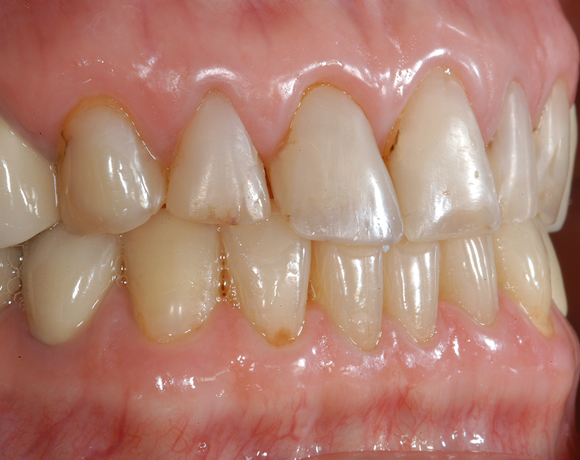

22 Einzelkronen mit Eris for E II

Empress II Presskeramik mit Eris Verblendkeramik bei einer Neuversorgung im Oberkiefer komplett und im Unterkiefer Vollkronen auf den Seitenzähnen.

Ein Projekt aus dem Jahr 2004

Hier wurden der ganze Oberkiefer und die Seitenzähne im Unterkiefer mit neuen Kronen aus Empress 2 und mit Eris Verblendkeramik versorgt.